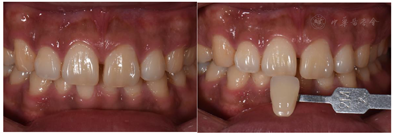

颌面外形对称,开口度及开口型正常,双侧颞下颌关节无明显异常,前牙浅覆合浅覆盖,下前牙中线偏右约1 mm;11、21间间隙约为2 mm,双侧磨牙均为安氏Ⅰ类关系,牙体色泽、形态无明显异常,叩(-),牙不松,牙龈无红肿及压痛,见图1、图2。口腔卫生情况一般,可见少量菌斑及烟斑;余未见明显异常。X线片示:11、21牙周膜间隙无明显增宽,根尖区未见明显异常。术前检查:

治疗计划为11、21贴面修复(邻面贴面)或正畸治疗。患者选择行贴面修复;龈上洁治,排龈,备牙前进行常规术前照相及比色(VITA2M2)。牙体预备:由11、21近中面扩展至唇近中线角,预备量约0.3 mm,基牙颈部预备与牙龈外形保持一致,肩台呈浅凹形,比色(VITA2M2)口扫;贴面试戴,邻接可,外形佳,与牙面边缘密合,色泽与天然牙匹配,患者满意同意粘接,粘结后检查正中颌、前伸颌及侧方颌,咬合无明显异常。见图3,图4,图5,图6,图7。